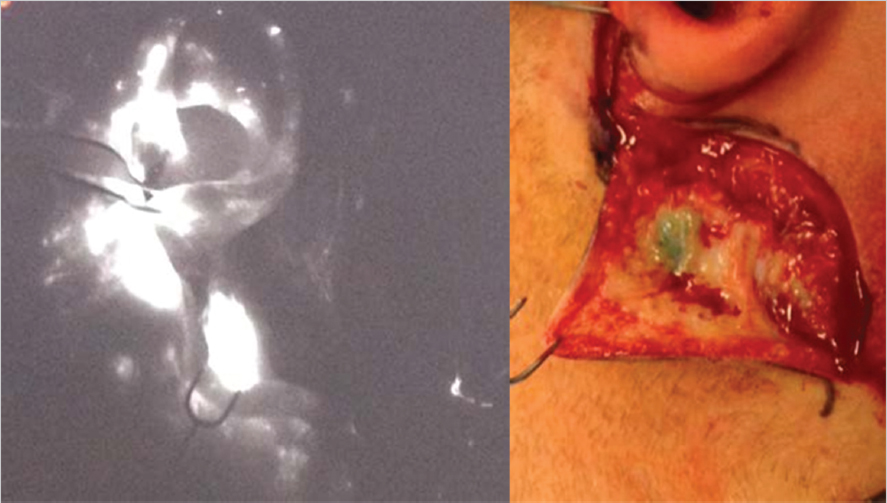

10 Operative Lymphadenectomy Malignant melanoma is the cutaneous malignancy that most often mandates an operative lymphadenectomy. The presence or absence of a positive lymph node in the draining basin is one of the most important prognostic factors in this disease. The rationale for a sentinel lymph node biopsy (SLNB) is discussed elsewhere in this text. For melanoma patients with positive SLNBs, lymph node dissection of the entire nodal basin is currently the standard of care in the United States. Other cutaneous malignancies for which a sentinel node biopsy and lymphadenectomy may be performed include Merkel’s cell carcinomas,1,2 high-risk squamous cell carcinomas (SCCs),3 cutaneous apocrine adenocarcinoma,4 and digital papillary adenocarcinomas.5 The concept of SLNB, as a minimally invasive technique to assess nodal involvement, was developed in 1977 by Cabanas, for the management of penile SCC.6 In 1992, Morton et al applied the same concept to the management of cutaneous melanoma, with the objective to reduce the morbidity related to lymph node dissection in these patients. The SLNB protocol is currently applied to other cutaneous malignancies as well.7 The assumption is that early detection of tumor cells in lymph nodes leads to a better prognosis by assisting in appropriate management by aiding the expeditious removal of other diseased lymph nodes in the affected basin. It also hones the indications for lymphadenectomy, by limiting the procedure only to those situations where an involved node has been definitively identified. This helps to limit the number of lymphadenectomies performed, consequently limiting the morbidity that they entail. In cutaneous melanomas, a completion lymphadenectomy performed for a positive SLN will reveal that only a small percentage of the dissection specimens examined will harbor more involved nodes—that is, nodes other than the sentinel node(s) containing malignant deposits. A representative figure of 15% was quoted by Elias et al from the Massachusetts General Hospital.8 Thus, there is scope for further refinement of this particular intervention. One idea is to use the SLNB as a stand-alone therapeutic procedure. This concept is currently being tested out in clinical trials. The concept of lymphoscintigraphy began with cadaveric studies in the 1800s when Cruickshank used intradermal mercury injections to demonstrate lymphatic drainage patterns.9 It was later discovered that lymphatic drainage is not as dogmatic and predictable as once thought. Although it is possible, based on population studies, to predict which basin a particular cutaneous zone will drain into, a great deal of variability exists, especially in the head/neck and trunk.10 Lymphoscintigraphy allows noninvasive preoperative identification of the primary nodal basin for cutaneous neoplasms.11 This imaging modality is especially valuable in lesions that have the potential to drain to several nodal basins. For example, lesions of the lower extremity can drain to the popliteal, femoral, inguinal, or iliac regions. In a similar fashion, lesions of the anterior scalp can drain to the intraparotid lymph nodes or levels I to V of the anterior cervical chain. In current practice, lymphoscintigraphy is performed by injecting a radiolabeled substance into the intradermal space around the tumor site so that the tracer can be taken up into the lymphatic system. The ideal radiolabeled injectable substance should have the following characteristics12: • It locates and demonstrates the sentinel lymph node without migrating further into the lymphatic chain. • It rapidly clears from the injection site to optimize ease of imaging the draining nodal basin. • The radiotracer should have a high detection rate but a short half-life and low particulate emission to minimize radiation dosage to health care personnel. Radiopharmaceuticals used for lymphoscintigraphy are principally technetium (Tc)-based labels and include 99m-Tc antimony sulfide, 99m-Tc rhenium sulfur colloid, and 99m-Tc albumin nanocolloid. In the United States, 99m-Tc sulfur colloid (50–2,000 nm particle size) is the most popular radiopharmaceutical. Typically, the filtered form of the compound is used. The use of a 0.2-μm filter eliminates particles larger than 200 nm, which allows for optimal uptake and transmission to the primary nodal basin for the lesion ( Identification of a sentinel node, however, does not mandate a lymphoscintigram. Vital dyes (isosulfan blue, methylene blue) have been used to duplicate the results of their radioactive counterparts. In this case, however, the identification of the sentinel lymph node cannot be performed in a noninvasive manner since the process of identification requires making an incision and visually identifying the appropriately stained node. A combination of 99m-Tc sulfur colloid and a blue dye has been reported to yield the best detection of sentinel nodes.13 A recent innovation has been the use of fluorescent imaging in the detection of sentinel lymph nodes.14,15,16 Indocyanine green (ICG), a tricarbocyanine dye with a molecular weight of 751.4Da, is the most commonly used compound for this purpose. ICG has been widely used for a variety of human studies, most commonly in ophthalmology, where it helps in delineating the retinal vasculature. In the context of sentinel node biopsies, the dye is injected in a peritumoral fashion analogous to its radioactive counterpart. The dye track and sentinel node are subsequently visualized using special imaging devices. The principle of fluorescence imaging is based on illuminating the target tissue with light at the excitation wavelength (□750–800 nm) while observing it at longer emission wavelengths, that is, greater than 800 nm. An additional benefit is that the green color of the dye can provide visual confirmation of the node ( Fig. 10.1 The injection site (small arrow) and the uptake in the axilla. Concurrent use of isosulfan blue confirmed the presence of the sentinel node. Note blue lymphatic vessel leading into node. Fig. 10.2 The injection site of ICG in front of the ear (held by forceps) and the uptake in the node adjacent to the skin hook. The visualized node is also stained green. A variety of other techniques such as quantum dots, receptor binding agents, and nanospheres have been used to visualize sentinel nodes on an experimental basis but have not yet been used routinely in the clinical arena. As previously mentioned, the sulfur colloid is injected intradermally to mimic lymphatic drainage of the primary lesion. Using a 25-gauge needle, the tracer is injected to surround the lesion or on both sides of the center of the incisional scar (if the primary tumor has already been excised) in four to six sites. Dynamic and static images are then obtained, 1 to 2 hours after injection, such that all potential nodal basins within the field are visualized. Each static image collection time should last approximately 5 to 10 minutes so that faintly labeled lymph nodes can be detected. The static images are obtained in standard views to allow adequate anatomic localization. Markers can be used to identify stable anatomic landmarks such as the ear canal or clavicle. The addition of SPECT/CT (single-photon emission computed tomography/computed tomography) allows tracer imaging to be superimposed on to the anatomic information obtained by CT and can be useful in head and neck primary melanomas.17 It is worthwhile to consider the timing of preoperative lymphoscintigraphy given that it can be obtained either days in advance of the proposed sentinel node biopsy or on the day of the procedure. Given the logistical issues described earlier regarding timing delays of image acquisition, it can be difficult to schedule lymphoscintigraphy on the day of the procedure. Obtaining imaging in advance of the operative intervention allows for review and confirmation with the interpreting nuclear medicine specialist. The other side of this argument is that a vast majority of these studies are straightforward and do not require detailed analysis. The typical practice is to inject the patient with the radionucleotide on the day of surgery. This obviates loss of the signal and any false positives that might result from the migration of the label into secondary or tertiary lymph nodes. Drainage patterns that do not conform to the norm are significantly more common in the head/neck and trunk.18,19 Interval nodes refer to the presence of nontraditional nodes situated in line of the drainage path between the site of the tumor and the main (traditional) drainage basin. In the head and neck, these patterns include drainage to the postauricular nodes from the anterior forehead or drainage to the occipital nodes from the scalp. Truncal melanomas may drain to the triangular intermuscular space, interpectoral nodes, interval nodes over the costal margin, or even retroperitoneal nodes. The epitrochlear and popliteal regions are a part of the normal lymphatic drainage patterns in the upper and lower limb, respectively, but their involvement is seen in less than 1% of cases ( As with the lymphoscintigram, the radiopharmaceutical is injected in four to six sites intradermally in a peritumoral location. This injection, depending on the institution, is done either by radiologists in the nuclear medicine suite or in the operating room by the surgeon. The uptake in the appropriate basin(s) is confirmed by a Geiger counter prior to the start of the procedure. Occasionally, this may take longer than 5 minutes, especially in the elderly with lower extremity melanomas. The vital dye, if used, can be injected in the operating room, after the induction of anesthesia to prevent unnecessary discomfort to the patient. In the interests of patient comfort, our practice is to inject the dye and the radiopharmaceutical after the induction of anesthesia. The site of the biopsy is included in the operating field and is appropriately prepared. If access to the node involves nerve stimulation, the anesthesiologist is informed, so that appropriate short-acting muscle relaxants are used, if indicated. We use prophylactic antibiotics that are administered immediately prior to the start of the procedure. Fig. 10.3 A subungual melanoma draining to epitrochlear node (smaller inferior dark circle) and a high axillary node (large dark circle) seen below left clavicular marker. The epitrochlear node contained metastatic melanoma. The experience of the last two decades has shown that the “hottest” node, that is, the node with the highest amount of radioactivity, does not translate into a guarantee that the malignant deposit will be found within it. In other words, a less radioactive lymph node may well be the abode of tumor cells. In 2008, Chung et al established 10% rule for SLN for breast cancer.20 These authors suggest that the removal of all the nodes with > 10% of radioactivity of the “hottest node” minimizes the false-negative rate of SLNB. The same criteria have been applied for SLNB in melanoma. Some other criteria used include radioactivity of 10 × background and even 3 × background.11 The sensitivity after removal of three “hot nodes” is 93 to 99% and that after removal of four nodes is 100%.21 The false-negative rate is 1 to 10% using the combined method (dye plus radionucleotide).22 Nonvisualization of sentinel lymph nodes may occur in some cases. In our experience, this has usually been seen in elderly men in the head and neck region. The proximity of the sentinel node site to the primary tumor may obscure the visualization of the sentinel node ( The presence of previous flap surgery may alter the flow pattern of the draining lymph vessels and thus yield false-negative results. In an analogous problem, the presence of a large scar (from an ill-advised attempt at an excisional biopsy) can generate misleading results if the entire length of the scar is included in the injection of the radiopharmaceutical. Under these circumstances, injecting the central part of the scar, the presumed site of the primary lesion, can yield satisfactory results ( Fig. 10.4 Intense radioactivity at site of injection of right mandibular melanoma obscuring sentinel node (left). Low-power histological section depicting resected skin at the 11 o’clock position and the rim of the lymph node (blue) at the 4 o’clock position. Occasionally, anatomic or surgical constraints may dictate whether a sentinel node is accessible ( The presence of a rich lymphatic network in and around the parotid gland complicates the harvest of sentinel nodes in the head and neck region.23 The preauricular lymph nodes, situated in the sulcus between the external auditory meatus and the parotid gland, are usually small and are therefore difficult to detect. This difficulty increases when the sentinel node is detected within the substance of the parotid gland. Based on traditional teaching, the recommended method of harvesting these nodes is via a superficial parotidectomy with a formal identification of the facial nerve in order to minimize the chances of damaging it. Another option is to directly access the sentinel node in the parotid using a classic facelift incision and carefully dissecting through the substance of the gland, using a nerve stimulator if necessary, to harvest the node.24 At our center, we have used both methods and currently prefer the technique of directly harvesting the sentinel node without a formal parotidectomy. In our series of 58 patients, we did not encounter a single case of facial nerve palsy. Interestingly, a survey of Head and Neck surgeons emphasized the wide variability in approaches to this problem, with as many as 48% of the surgeons surveyed opting for a superficial parotidectomy.25 It must be emphasized that the parotid sparing approach for sentinel node harvest should only be undertaken by experienced surgeons, failing which a parotidectomy is always the safer option. Frozen sections, in general, are not recommended for the analysis of sentinel nodes in melanomas.26 These require a special expertise on the part of the examining pathologists which may not be universally available. The presence of benign nevus cells in the subcapsular region that may be mistaken for cells of metastatic melanoma further heightens the degree of uncertainty during such analyses. A final consideration for lymphoscintigraphy in melanoma (and other malignancies) is how lymphatic drainage and therefore radiotracer localization may be affected by regional meta-static disease. There is evidence that micrometastases do not affect mapping techniques or SLNB identification. Additionally, there are some studies that demonstrate normal or near-normal lymphatic drainage patterns despite lymph node metastases. Sentinel node biopsies, generally speaking, are very safe procedures. Seromas and hematomas probably constitute the most common problems. To limit the occurrence of the former problem, we are liberal in the use of drains in our practice. Wound-healing problems such as infection and wound dehiscence are similarly rare. There have been reports of lymphedema occurring after the harvest of sentinel nodes alone but these situations, too, are extremely rare. Planning for operative lymphadenectomy begins with thorough history and physical exam at the initial encounter with the patient. Neck, groin, or axillary bulges, masses, or discomfort can be the first presentation of a clinically positive regional lymph node in a patient with melanoma and rarely in other cutaneous cancers. Physical exam should include examination of all possible drainage basins based on tumor location. Factors in this exam might be of considerable importance in the conduct of these procedures. Some examples include the presence of previous scars that might modify placement of incisions or impact the vascularity of poorly placed ones, problems affecting the cervical spine or the shoulder which might limit optimal positioning and exposure of the operative site of the patient, or the presence of inguinal of femoral hernias that might go unnoticed or unrecognized leading to possible damage in the dissections of this area. Certain common features apply to the dissection of the major lymph nodal basins, that is, cervical, axillary, and inguinofemoral and pelvic basins. • Positioning is of utmost importance. A poorly positioned patient can significantly add to operating time. • Communication with the anesthesia team is critical if nerve testing is to be performed so that long-acting paralytic agents are not administered. • The resection of large tumor masses that may result in significant bleeding should necessitate a preoperative type and cross-match of blood, if this is not routinely performed. • Along the same lines, if an unusually long or bloody procedure is anticipated, the preoperative placement of a Foley catheter may be helpful. This is mandatory in patients with pelvic or groin dissection to prevent inadvertent damage to the bladder, especially in the elderly. Fig. 10.8 Melanoma (circled) in a patient with history of spinal fusion with rib harvest from left chest wall and a midline incision over the spinous processes for Harrington’s rod placement. Lymphoscintigram revealed drainage to paravertebral nodes. An attempt at biopsy was abandoned owing to difficulty of access under Harrington’s rods. • Sequential compression devices are routinely used on the lower extremities to prevent deep vein thrombosis. • Postoperatively, one must be vigilant about lymphedema, especially with the lower limb, pelvic, and groin dissection and to a lesser degree in the upper limb. The importance of this preoperative discussion cannot be overemphasized. The prophylactic use of controlled pressure stockings may be of some benefit in high-risk patients, such as the obese ones. • The adequacy of the lymphadenectomy can be judged using the number of nodes harvested during the procedure. Thus, Spillane and colleagues from the Sydney Melanoma Unit offer the following benchmarks.27 Axillary dissections should aim for a minimum of 10 nodes, inguinal and ilioinguinal dissections for a minimum of 7 nodes, and cervical lymph node dissections involving 4 or more levels should aim for a minimum of 20 nodes. The cervical lymph nodes are the most common initial site of regional metastases for melanomas of the head and neck. As mentioned previously, patterns of lymphatic spread can generally be predicted based on the location of the primary tumor. The anterior scalp, ear, and face typically drain first to the intraparotid node. These structures as well as the anterior neck can also drain to the cervical nodes including levels I to V ( The posterior scalp and posterior neck typically drain to level V cervical nodes as well as the retroauricular and suboccipital node. The discussion of head and neck lymphadenectomy is incomplete without a mention of SCCs of the lip and cheek. SCCs account for nearly 95% of lip cancers. The size of the primary tumor is one of the most significant predictors for prognosis.28 For example, T2 lesions have a 5-year survival rate of approximately 90%, while T3 lesions have a 40 to 60% survival rate at 5 years. Regional metastases to the lymphatic system seem to occur less frequently in SCCs of the lip as compared to other SCCs of the head and neck. Lower lip SCCs metastasize to the submandibular nodes in 70 to 90% of cases of regional spread.28 Isolated nodal spread is present in 75% of regional metastases for SCCs of the lip, and 25 to 45% of these cases involved the submental, level I nodes. SCCs of the upper lip typically spread to the submandibular or lower intraparotid nodes. Fig. 10.9 Division of nodal groups by subzones in both lateral (left) and anterior view (right). Level I: Submental and submandibular nodes. This group includes the lymph nodes located within the submental triangle, bounded by the anterior belly of the digastric muscle and the hyoid bone. The submandibular group includes the lymph nodes located within the boundaries of the anterior and posterior bellies of the digastric muscle, the stylohyoid muscle, and the body of the mandible. The submandibular gland, which is located within this cervical space, should be removed when this nodal group is included in the resection. IA, submental nodes; IB, submandibular nodes. Level II: Upper jugular nodes. This group contains the lymph nodes located around the upper third of the internal jugular vein and the spinal accessory nerve. It goes from the level of the skull base superiorly to the level of the inferior border of the hyoid bone and carotid bifurcation inferiorly. The posterior boundary is the posterior border of the sternocleidomastoid muscle, and the anterior boundary is the lateral border of the sternohyoid and stylohyoid muscles. IIA, upper jugular nodes anterior to the XI nerve; IIB, upper jugular nodes posterior to the XI nerve. Level III: Middle jugular nodes. This group includes the lymph nodes located around the middle third of the internal jugular vein. The boundaries of this space are the inferior border of the hyoid bone and the carotid bifurcation superiorly, the inferior border of the cricoid cartilage, and the junction of the omohyoid muscle with the internal jugular vein inferiorly, the posterior border of the sternocleidomastoid muscle posteriorly, and the lateral border of the sternohyoid muscle anteriorly. Level IV: Lower jugular nodes. This nodal group contains the lymphatic structures located around the lower third of the internal jugular vein. Its boundaries are the inferior border of the cricoid cartilage and the omohyoid muscle superiorly, the clavicle inferiorly, the posterior border of the sternocleidomastoid muscle posteriorly, and the lateral border of the sternohyoid muscle anteriorly. Level V: Posterior triangle. This group includes the lymph nodes located along the transverse cervical artery and lower half of the spinal accessory nerve as well as the supraclavicular lymph nodes. The boundaries are the anterior border of the trapezius muscle posteriorly, the posterior border of the sternocleidomastoid muscle anteriorly, the clavicle inferiorly, and the convergence of the sternocleidomastoid and trapezius muscles superiorly. VA, lymph nodes in the posterior triangle located above the level of the inferior border of the cricoid cartilage; VB, lymph nodes in the posterior triangle located below the level of the inferior border of the cricoid cartilage. Level VI: Anterior compartment. This level contains the pre- and paratracheal nodes, precricoid (Delphian) node, perithyroidal nodes, and the lymph nodes along the recurrent laryngeal nerves. The boundaries are the hyoid bone superiorly, the suprasternal notch inferiorly, and the carotid arteries laterally.

Fig. 10.1).

Fig. 10.2). Further research is warranted to reliably establish the efficacy and utility of ICG for SLNB.